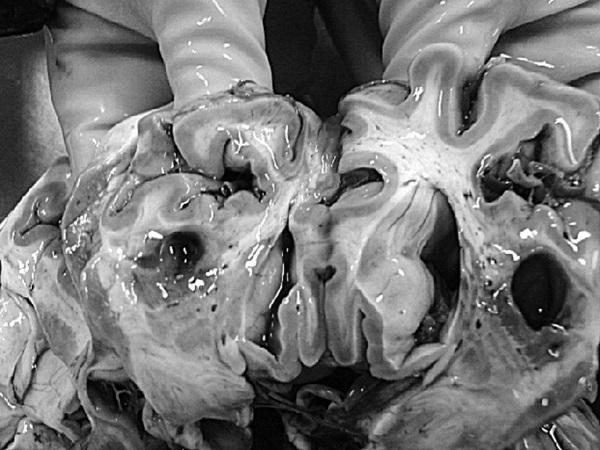

На секции был установлен следующий диагноз.

Основной:

1. Последствия инфаркта головного мозга. Внутренняя гидроцефалия. Атеросклероз артерий виллизиева круга.

2. ИБС. Постинфарктный кардиосклероз. Атеросклероз коронарных артерий.

Фоновый:

1. Артериальная гипертензия.

2. Гипертрофия левого желудочка сердца.

Осложнения:

1. Длительная иммобилизация.

2. Хроническая сердечная недостаточность.

3. Невроангиосклероз.

4. Пролежни.

5. Интоксикация.

6. Отек головного мозга.

Сопутствующий:

Доброкачественная гиперплазия предстательной железы

Последствия ОНМК: постинфарктные кисты головного мозга

Постинфарктный кардиосклероз